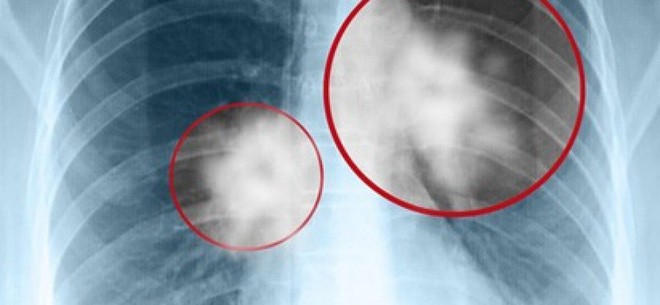

Đây là những người nhất định phải đi khám sức khỏe phổi định kỳ hàng năm, đặc biệt là chụp X-quang phổi để sớm phát hiện những thay đổi bất thường.

Nếu bị mắc bệnh lao lâu ngày, mỗi lần đi kiểm tra sức khỏe của phổi bằng cách chụp hình ảnh ngực, bạn nên so sánh với kết quả đi khám trước đó thông qua tấm phim chụp.

Nếu kết quả so sánh những ảnh chụp X-quang ngực lần trước và lần sau cho thấy hình dạng, kích thước bản chất của phổi có sự thay đổi, thì cần lưu ý rằng bệnh ung thư có thể đang có xu hướng phát sinh và tấn công bạn.

Những hình ảnh cũ và mới trong những tấm phim chụp phổi sẽ giúp bạn so sánh tình trạng sức khỏe phổi trong hiện tại và quá khứ, từ đó có thể có những nhận định về tình trạng phát triển của bệnh.

Đừng bỏ qua những triệu chứng đơn giản, kể cả những người bị viêm phổi tái phát nhiều lần cũng nên thường xuyên đi kiểm tra phổi, loại bỏ những nguy cơ mắc bệnh, trong trường hợp nghiêm trọng thì nên chụp CT để kiểm tra chi tiết nếu thấy cần thiết.

Những nhóm người có nguy cơ ung thư phổi, đặc biệt là nhóm người đã liệt kê ở trên nên chú ý kiểm tra sức khỏe định kỳ, chụp CT ngực thường xuyên để phát hiện sớm và điều trị sớm, từ đó có thể làm giảm tỷ lệ tử vong do ung thư phổi.